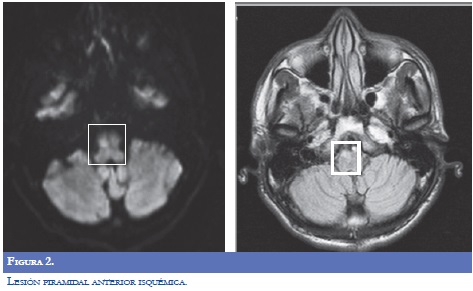

Paraclínicos de ingreso: glucometría 272 mg/ dl, Hb Glicosilada 15,8%. La RM del encéfalo (9/09/2009): evidenció lesión que restringía la difusión, visible en FLAIR y T2, infarto subagudo en región superior y anterior derecha del bulbo raquídeo. Imagen hiperintensa en T1, que no realzaba, en el tálamo derecho. Angioresonancia: fenestración de la arteria vertebral derecha distal, hallazgo incidental Neuroradiología reportó que la lesión hiperintensa talámica derecha pudiera obedecer a alteración metabólica por hiperglicemia, pero fue asumido por neurología clínica como infarto lacunar (Figuras 1-2).

Se inició terapia física basada en estiramientos pasivos sostenidos, movilizaciones pasivas por medio de patrones unilaterales, posicionamiento, fortalecimiento muscular, entrenamiento de agarre fino y grueso y entrenamiento del patrón de marcha sin caminador, equilibrio y propiocepción. Mejoró a paresia braquial izquierda 3/5 y 4/5 crural ipsilateral, hipotónico, con Babinski izquierdo. Parestesias de hemicuerpo izquierdo. Logró marcha parética, muy limitada. Valoración de egreso (18/09/2009): lesión talámica derecha que sugiere infarto lacunar con transformación hemorrágica. Se descartó cardioembolismo, estenosis intracraneana o extracraneana, trombofilia o autoinmunidad. Por ser diabético mal controlado, se atribuyó la causa del ACV a microangiopatía.

Los diagnósticos de egreso (18/09/2009) fueron: ACV bulbar superior y anterior derecho en paciente joven; infarto lacunar talámico derecho con transformación hemorrágica; Diabetes insulino requiriente descompensada.

La causa atribuida al cuadro neurológico que presentó el paciente correspondió a infartos lacunares secundarios a microangiopatia diabética en el talámo y la pirámide bulbar derechos. El infarto de la pirámide bulbar derecha explica una lesión parcial de la vía córtico espinal previa a la decusación. De esta forma dicho déficit explica la hemiplejia izquierda inicial. La ubicación de esta lesión no explica la sintomatología sensitiva. La lesión talámica derecha, en la zona medial, explica la sintomatología sensitiva. La arteria cerebral posterior, mediante su rama geniculotalámica, perfunde el territorio talámico posterolateral. La arteria comunicante posterior, a través de la rama tuberotalámica, riega el territorio talámico anterolateral. La arteria carótida interna, por su rama coroidea anterior, se distribuye en el territorio talámico lateral (13).